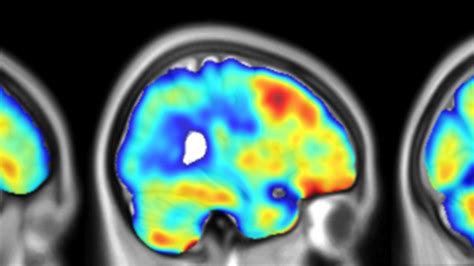

So, what exactly is a PET scan, and how does it help us understand dementia on a PET scan ? PET stands for Positron Emission Tomography. Think of it as a highly advanced way to look inside the brain, not just at its structure (like an MRI or CT scan), but at its activity . It uses a special radioactive tracer, which is a tiny amount of a radioactive substance, that is injected into your bloodstream. This tracer travels through your body and collects in areas of your brain that have high levels of chemical activity. Different tracers can be used to highlight different processes in the brain. For instance, one common tracer, FDG (fluorodeoxyglucose), is a form of sugar that your brain cells use for energy. Areas of the brain that are more active will use more glucose, and therefore, will pick up more of the FDG tracer. A special camera then detects the signals emitted by the tracer, and a computer uses this information to create detailed, three-dimensional images of the brain. These images show us how well your brain cells are working and communicating. In the context of dementia, a PET scan can reveal patterns of reduced brain activity or the presence of abnormal proteins that are hallmarks of diseases like Alzheimer’s. It’s like giving your brain a functional check-up, pinpointing areas that might be struggling even before significant symptoms become obvious. This allows for earlier and more accurate diagnoses, which is crucial for managing dementia and exploring treatment options. The insights gained from PET scans can also help differentiate between various types of dementia, as different conditions affect the brain in unique ways. It’s a powerful tool in the neurologist’s arsenal, offering a window into the complex world of brain health and disease.

Now, let’s get down to the nitty-gritty: how do these PET scans actually detect dementia on a PET scan ? It’s all about what the tracers can highlight. As we mentioned, the most common tracer used for dementia is FDG. In a healthy brain, glucose metabolism is typically high in certain areas, especially the cerebral cortex, which is responsible for thinking, memory, and language. In individuals with dementia, especially Alzheimer’s disease, certain brain regions show a decrease in glucose metabolism. This means those brain cells aren’t using as much energy, indicating they are less active and possibly damaged or dying. The PET scanner picks up these ‘dimmer’ spots, showing us where the brain’s activity is reduced. For Alzheimer’s, this often occurs first in the temporal and parietal lobes, areas critical for memory and cognitive function. But PET scans aren’t limited to just looking at metabolism. Other specialized tracers can detect the abnormal protein buildups that are characteristic of certain dementias. For example, amyloid PET scans use tracers that bind to amyloid plaques, sticky protein clumps that accumulate in the brains of people with Alzheimer’s. Seeing these plaques, even in individuals who are not yet showing significant symptoms, can help confirm an Alzheimer’s diagnosis or assess the risk. Similarly, tau PET scans can detect tau tangles, another hallmark protein abnormality in Alzheimer’s and other tauopathies. These advanced imaging techniques provide crucial diagnostic information that can be difficult to obtain through other methods alone. It’s like having a detective that can specifically find the clues left behind by the disease, offering a much clearer picture of what’s happening at a cellular level. This diagnostic precision is invaluable for guiding treatment strategies and research efforts. The ability to visualize these pathological changes directly offers unprecedented insights into the progression and impact of neurodegenerative diseases.

Guys, when we talk about dementia on a PET scan , it’s not just one size fits all. There are actually different types of PET scans, each designed to look for specific things related to dementia. The most common one you’ll hear about is the FDG-PET scan . As we touched on, FDG is a radioactive sugar. Your brain gobbles up sugar for energy. So, an FDG-PET scan basically shows us a map of your brain’s energy consumption. In people with dementia, especially Alzheimer’s, you’ll often see ‘cold spots’ – areas where there’s less sugar being used. This indicates reduced brain activity, often in specific patterns that can help differentiate between different types of dementia. For instance, Alzheimer’s typically shows reduced activity in the temporal and parietal lobes, while frontotemporal dementia might show changes in the frontal and temporal lobes. It’s a fantastic way to see how the brain is functioning . Then, we have the more specialized scans like Amyloid PET scans . These use tracers that specifically bind to amyloid plaques, those sticky protein clumps that build up in the brains of people with Alzheimer’s. Seeing these plaques directly can be a really strong indicator of Alzheimer’s disease, even in the early stages. This can be super helpful because sometimes amyloid plaques can start building up years before any noticeable symptoms appear. Lastly, there are Tau PET scans . Tau is another protein that forms abnormal tangles inside brain cells in Alzheimer’s and other neurodegenerative diseases. Tau PET scans can detect these tangles. The location and amount of tau buildup can actually give clues about the disease’s progression and severity. So, imagine having these different lenses to look through – one showing energy use, another showing plaque buildup, and a third showing tangle formation. Together, they give doctors a comprehensive picture of what’s happening in the brain, making the diagnosis of dementia on a PET scan much more precise and informative. This multi-faceted approach allows for a more nuanced understanding of the underlying pathology, aiding in both clinical management and the development of targeted therapies. The ability to visualize these specific molecular targets provides a significant advantage over traditional diagnostic methods, offering hope for more effective interventions.

Let’s zoom in on Alzheimer’s disease, because this is where dementia on a PET scan really shines. When doctors suspect Alzheimer’s, a PET scan can provide critical information that goes beyond what we can see on structural imaging like MRIs. An FDG-PET scan can reveal characteristic patterns of hypometabolism , meaning reduced glucose uptake, in specific brain regions. For Alzheimer’s, this typically shows up first in the posterior cingulate cortex, precuneus, and areas of the temporal and parietal lobes. These are the memory and thinking centers, so it makes sense that they’d be affected early on. Seeing these ‘dim spots’ can be a strong sign that Alzheimer’s is present, helping to distinguish it from other conditions that might cause cognitive decline. Beyond just looking at general brain activity, Amyloid PET scans are revolutionizing how we diagnose Alzheimer’s. These scans can detect the buildup of amyloid-beta plaques, which are one of the primary culprits in Alzheimer’s pathology. The presence of a significant amyloid burden, visualized on the scan, is a key diagnostic criterion for Alzheimer’s disease. It’s like finding the smoking gun – the physical evidence of the disease process. Even before significant memory loss or confusion sets in, amyloid plaques can be accumulating. An amyloid PET scan can identify this buildup, offering a window into the very early stages of the disease. Furthermore, Tau PET scans are increasingly important. Tau tangles are another hallmark of Alzheimer’s, and their distribution often correlates with the severity of cognitive impairment and the progression of the disease. By visualizing where tau pathology is concentrated, doctors can get a better sense of how advanced the disease is and predict its likely course. So, for Alzheimer’s specifically, dementia on a PET scan offers a powerful, multi-pronged approach: it shows us where the brain is struggling functionally (FDG-PET), confirms the presence of key pathological proteins like amyloid (Amyloid PET), and can even map the spread of tau tangles (Tau PET). This comprehensive diagnostic picture is invaluable for patients and their families, paving the way for more informed discussions about prognosis and treatment. The cumulative evidence from these different PET imaging modalities allows for a much higher degree of diagnostic certainty and can guide therapeutic strategies more effectively.